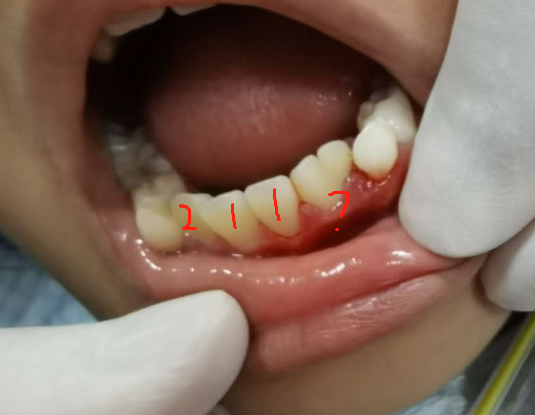

(下图是融合牙,这算两颗牙齿还是一颗牙齿?)

(上图为先天缺失两颗牙齿)